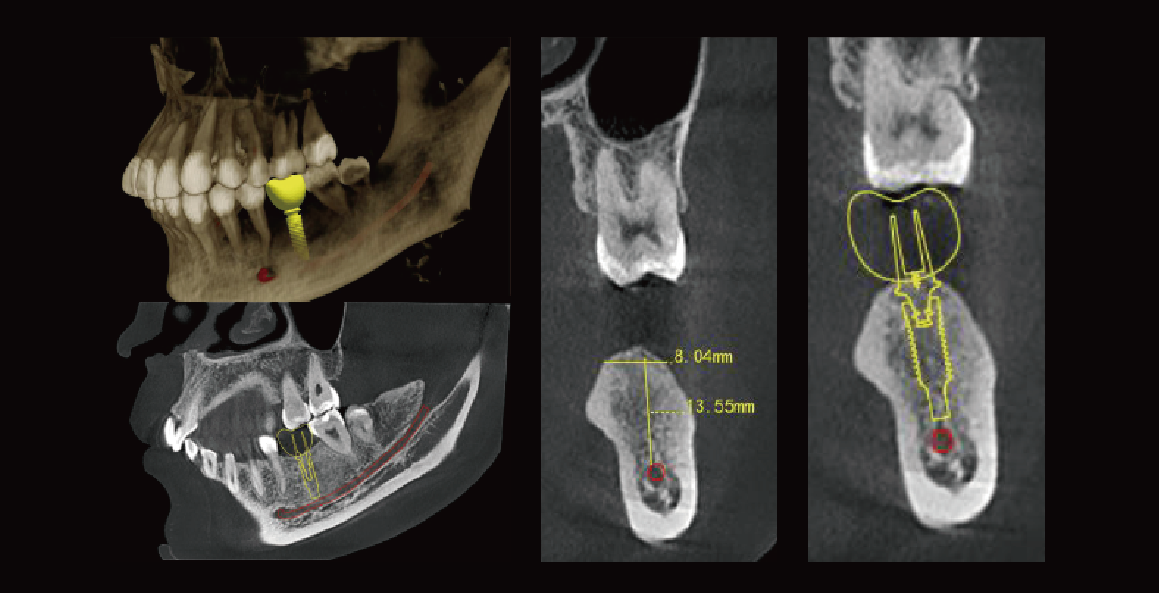

Implant Simulation

Neural tubes will be highlighted, which presents a relationship between the location of the implant and optimal length. This is the best way to improve the success rate for implant surgery.